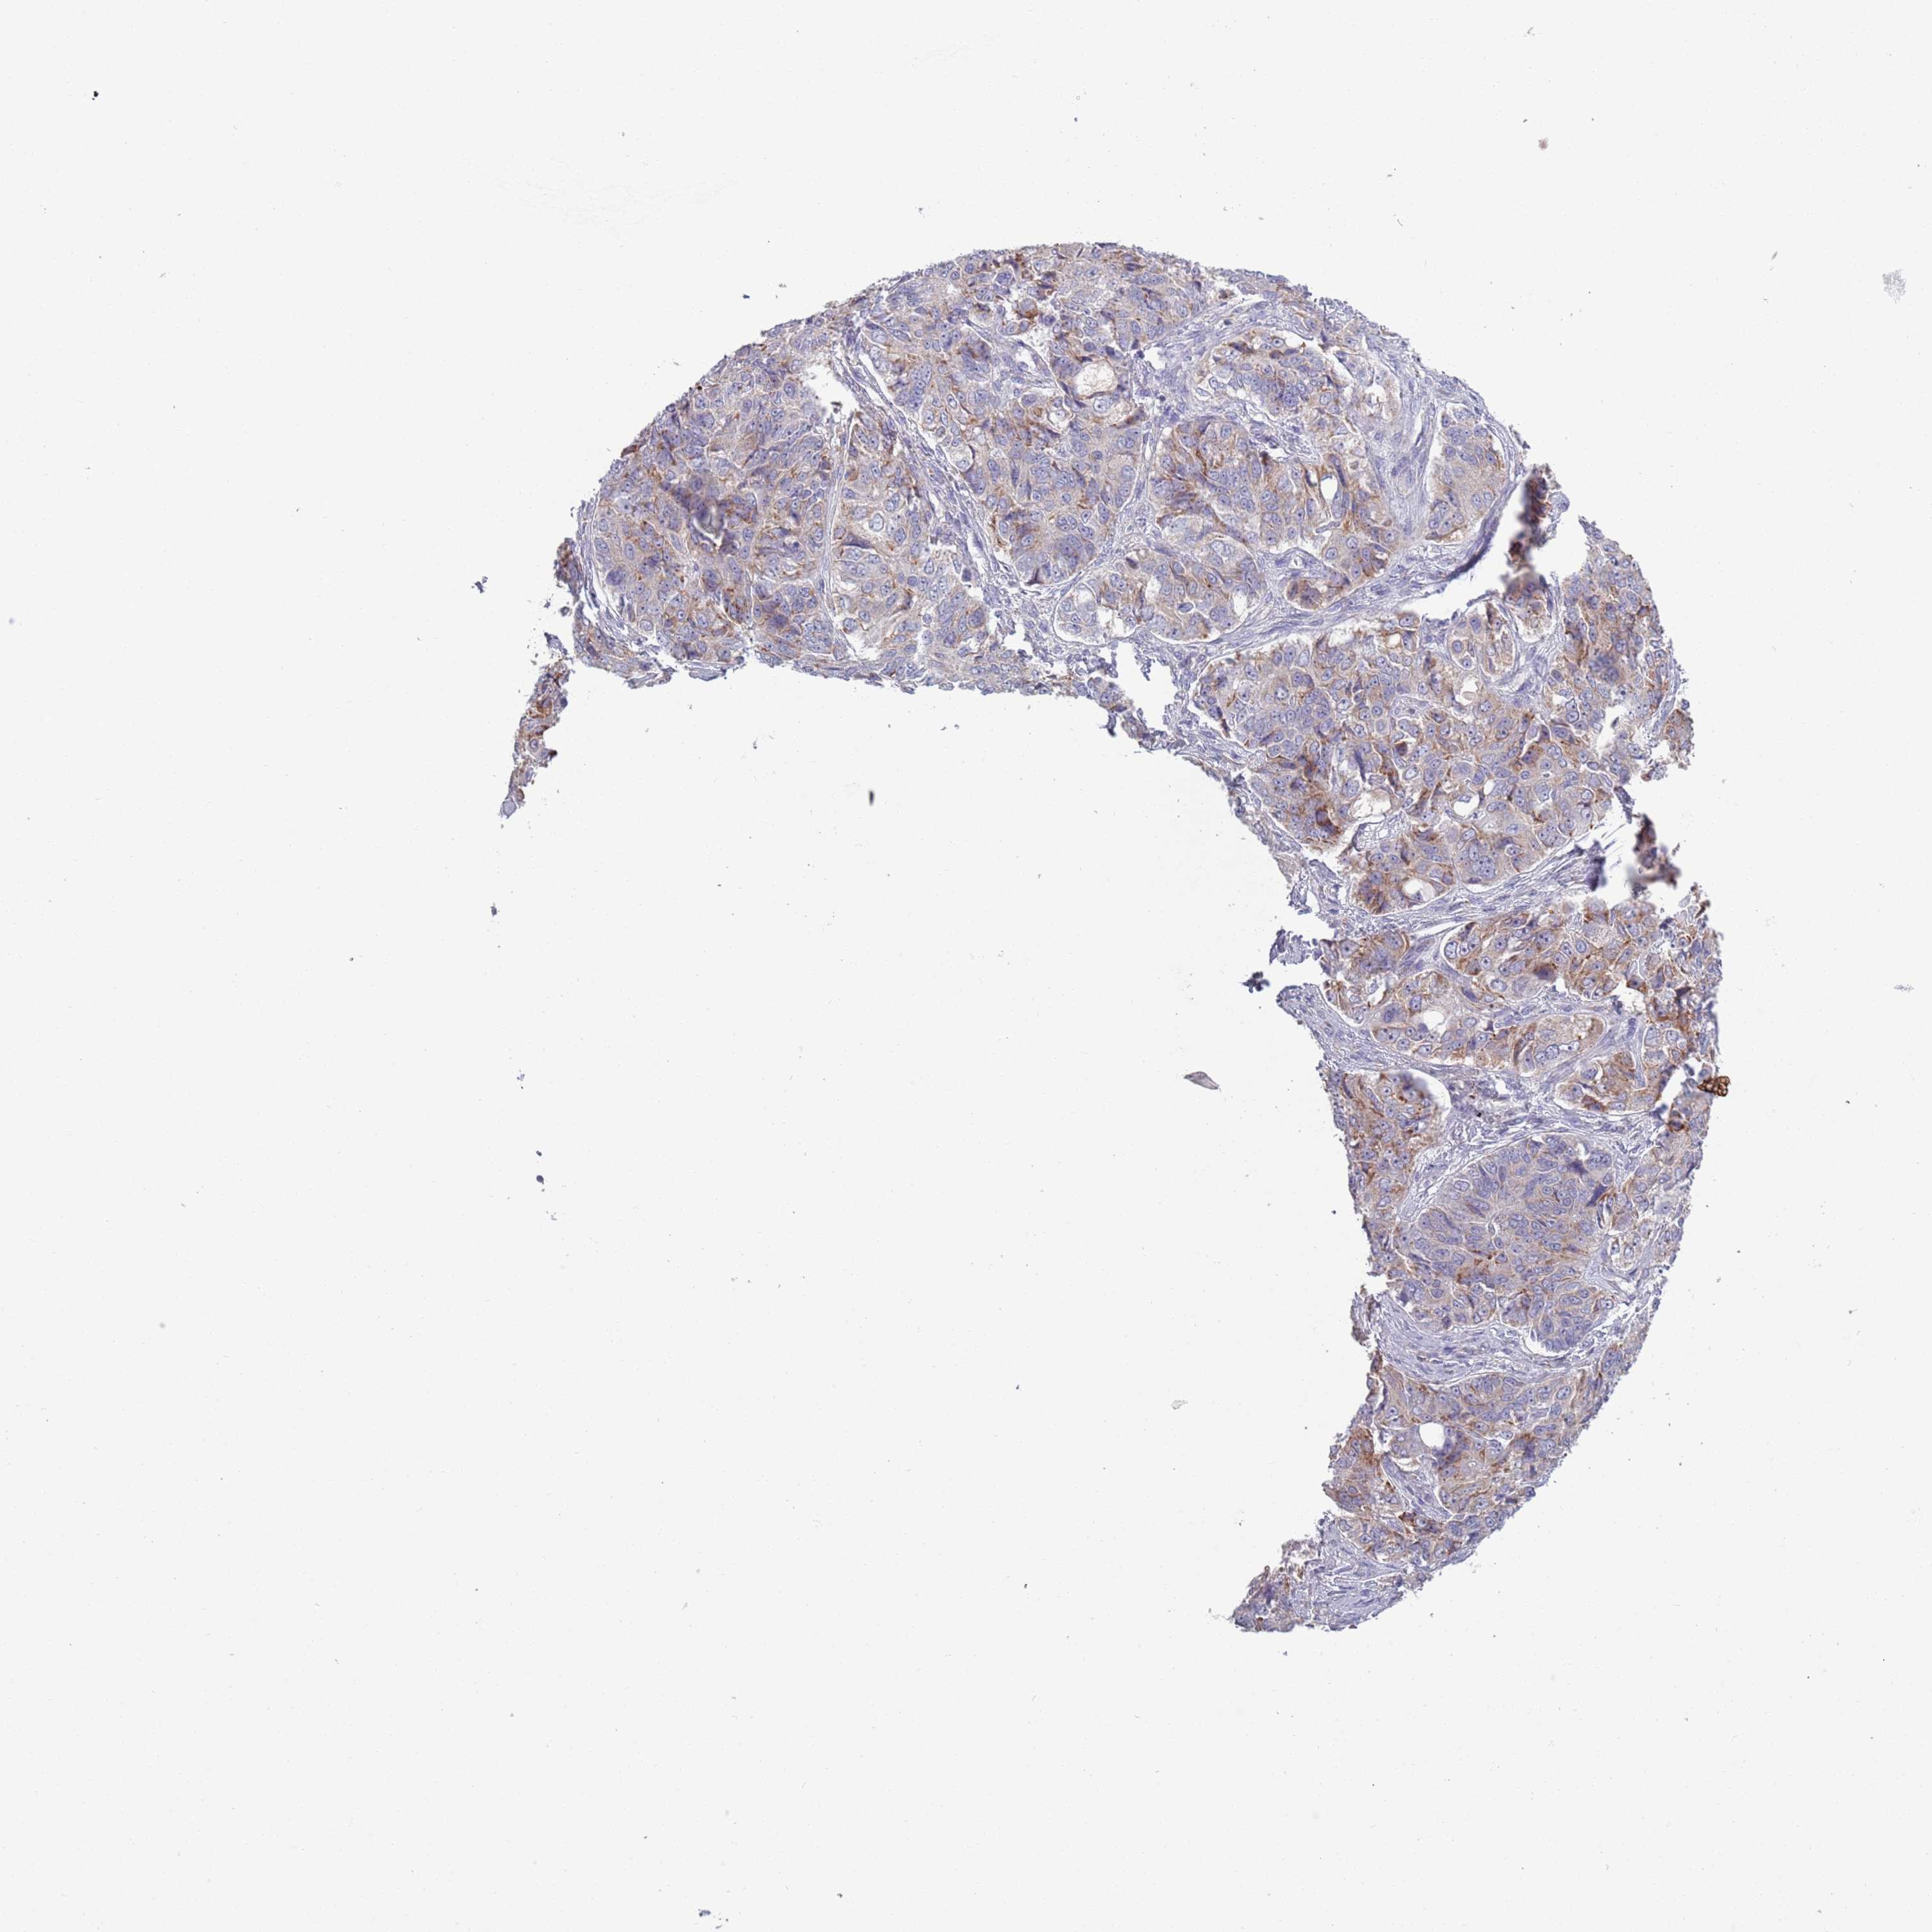

OVARIAN CANCER - Protein expressioni

A mouse-over function shows sample information and annotation data. Click on an image to view it in a full screen mode. Samples can be filtered based on level of antibody staining by selecting one or several of the following categories: high, medium, low and not detected. The assay and annotation is described here.

Note that samples used for immunohistochemistry by the Human Protein Atlas do not correspond to samples in the TCGA dataset.

Antibody stainingi

Antibody staining in the annotated cell types in the current human tissue is reported as not detected, low, medium, or high, based on conventional immunohistochemistry profiling in selected tissues. This score is based on the combination of the staining intensity and fraction of stained cells.

Each image is clickable and will lead to virtual microscopy that enables deeper exploration of all samples and also displays staining intensity scores, fraction scores and subcellular localization as well as patient and tissue information for each sample.

Antibody HPA048884

Staining

High

Medium

Low

Not detected

Intensity

Strong

Moderate

Weak

Negative

Quantity

>75%

75%-25%

<25%

None

Location

Nuclear

Cytoplasmic/membranous

Cytoplasmic/membranous,nuclear

Cystadenocarcinoma, serous, NOS

Carcinoma, NOS

Cystadenocarcinoma, mucinous, NOS

Carcinoma, endometroid